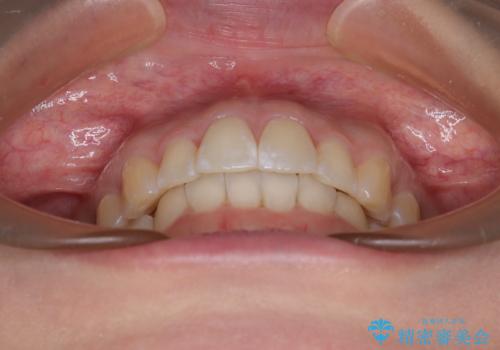

前に飛び出して目立っている前歯を整える インビザライン矯正治療

- 前方に主張した前歯2本を気にして来院された患者様です。

下顎前歯がデコボコしており、その影響で上顎前歯が前方に押し出されている状態でした。

口元が閉じにくいという印象はなかったため、非抜歯矯正にて歯列を整えていくこととしました。

上下左右の親知らずを抜歯し、上下ともに歯列を後方と側方に拡大し、口元を突出させることなくデコボコを解消することとしました。

前歯の形が台形であり、歯列が整ったところでブラックトライアングルが目立つ仕上がりとなったため、IPR(歯と歯の間を削る処置)によって歯の形態を修正し、隙間の目立たない歯列に仕上げることができました。